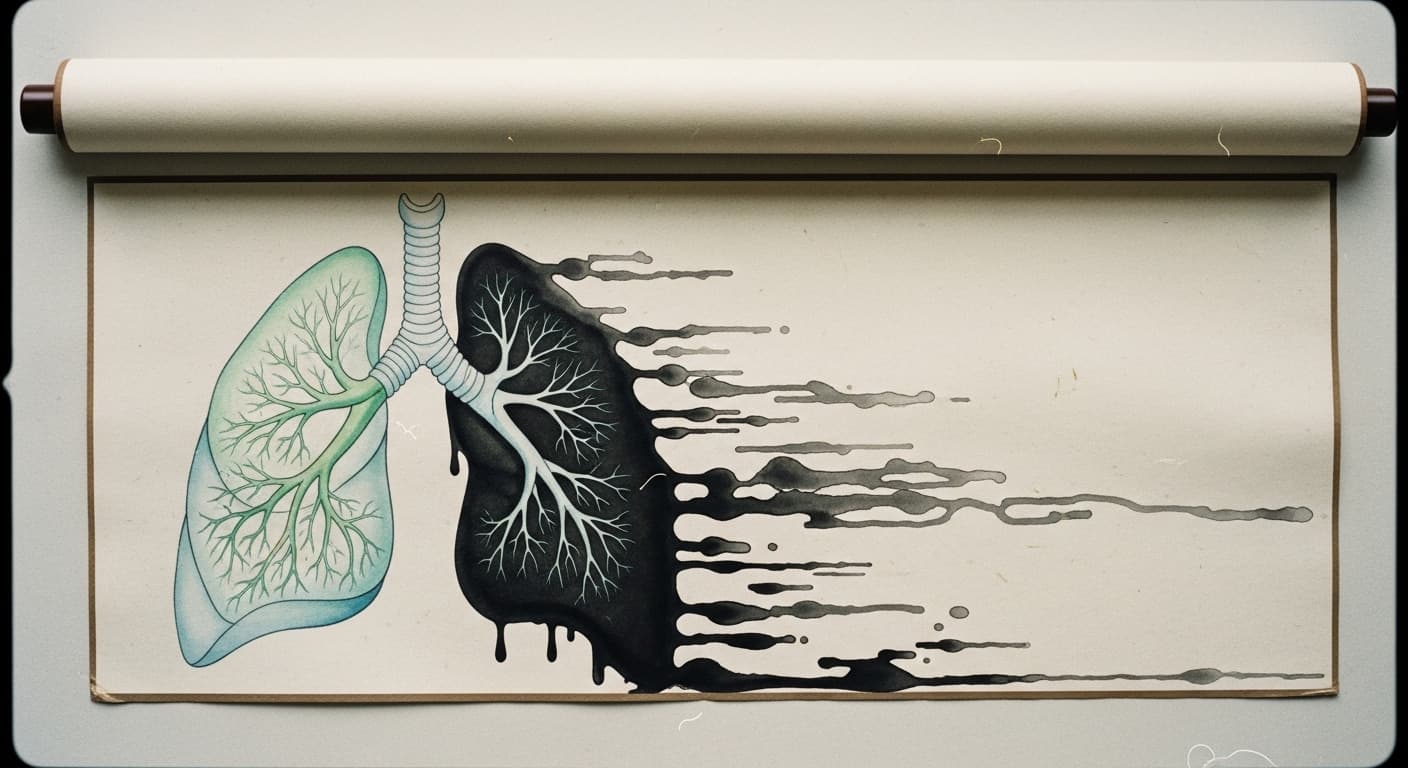

감기는 바이러스 감염으로 인한 급성 호흡기 질환이지만, 바이러스는 우리 몸에서 사라져도 그 흔적은 오래도록 남을 수 있어요. 바로 '만성 기침'이라는 형태로 말이죠. 현대 의학에서는 감기 후 한 달 이상 지속되는 기침을 '만성 기침'으로 분류하는데, 이는 동의보감에서 말하는 '폐에 병이 든 것'과 맥락을 같이 합니다. 감기 바이러스가 폐와 기관지를 침범하면, 우리 몸은 염증 반응을 일으켜 바이러스와 싸워요. 이 과정에서 기관지 점막이 손상되고 과민해지는데, 바이러스가 사라진 후에도 염증 반응이 완전히 가라앉지 않거나, 손상된 점막이 완전히 회복되지 않으면 기관지가 계속 자극에 예민하게 반응하게 됩니다. 이를 '기관지 과민성'이라고 하는데, 먼지, 찬 공기, 매연, 건조한 공기 등 사소한 자극에도 기침 반사가 쉽게 유발되는 상태를 말해요. 더 나아가, 만성 기침은 단순히 기관지의 문제만을 넘어설 수 있어요. 바이러스 감염은 우리 몸의 신경계에도 영향을 미칠 수 있답니다. 특히 미주신경(Vagus nerve)은 폐와 기관지를 포함한 다양한 내장 기관의 감각과 운동을 조절하는데, 감염 후 미주신경이 과도하게 활성화되거나 민감해지면 기침 반사 회로가 지속적으로 자극될 수 있어요. 뇌의 기침 중추는 평소보다 작은 자극에도 '기침!'이라는 명령을 내리게 되는 거죠. 또한, 위식도 역류 질환(GERD)이나 후비루 증후군(Upper Airway Cough Syndrome, UACS)도 만성 기침의 흔한 원인입니다. 위산이 역류하여 식도를 자극하거나, 콧물이나 분비물이 목뒤로 넘어가는 것이 기침을 유발하는 거죠. 동의보감에서 '담음'이 폐를 막는다고 표현했던 것처럼, 현대 의학에서도 과도한 점액 분비나 위산 역류가 기관지를 자극하여 기침을 일으킨다고 봅니다. 이는 단순히 폐 자체의 문제뿐만 아니라, 소화기계나 상기도의 불균형이 전신적인 호흡기 증상으로 나타날 수 있음을 시사해요. 더욱 중요한 것은, 이러한 만성 기침이 심리적인 스트레스와 상호작용한다는 점입니다. 기침 때문에 잠을 못 자거나 일상생활에 지장을 받으면 스트레스 호르몬인 코르티솔 수치가 높아지고, 이는 면역 기능을 저하시켜 염증 반응을 악화시키고 기관지 과민성을 더욱 심화시킬 수 있어요. 신경내분비계의 불균형이 만성 기침의 고리를 더욱 단단하게 만드는 셈이죠. 따라서 만성 기침은 단순히 폐만의 문제가 아니라, 우리 몸의 면역계, 신경계, 소화기계, 심지어 정신적인 상태까지 아우르는 복합적인 접근이 필요한 질환이랍니다.